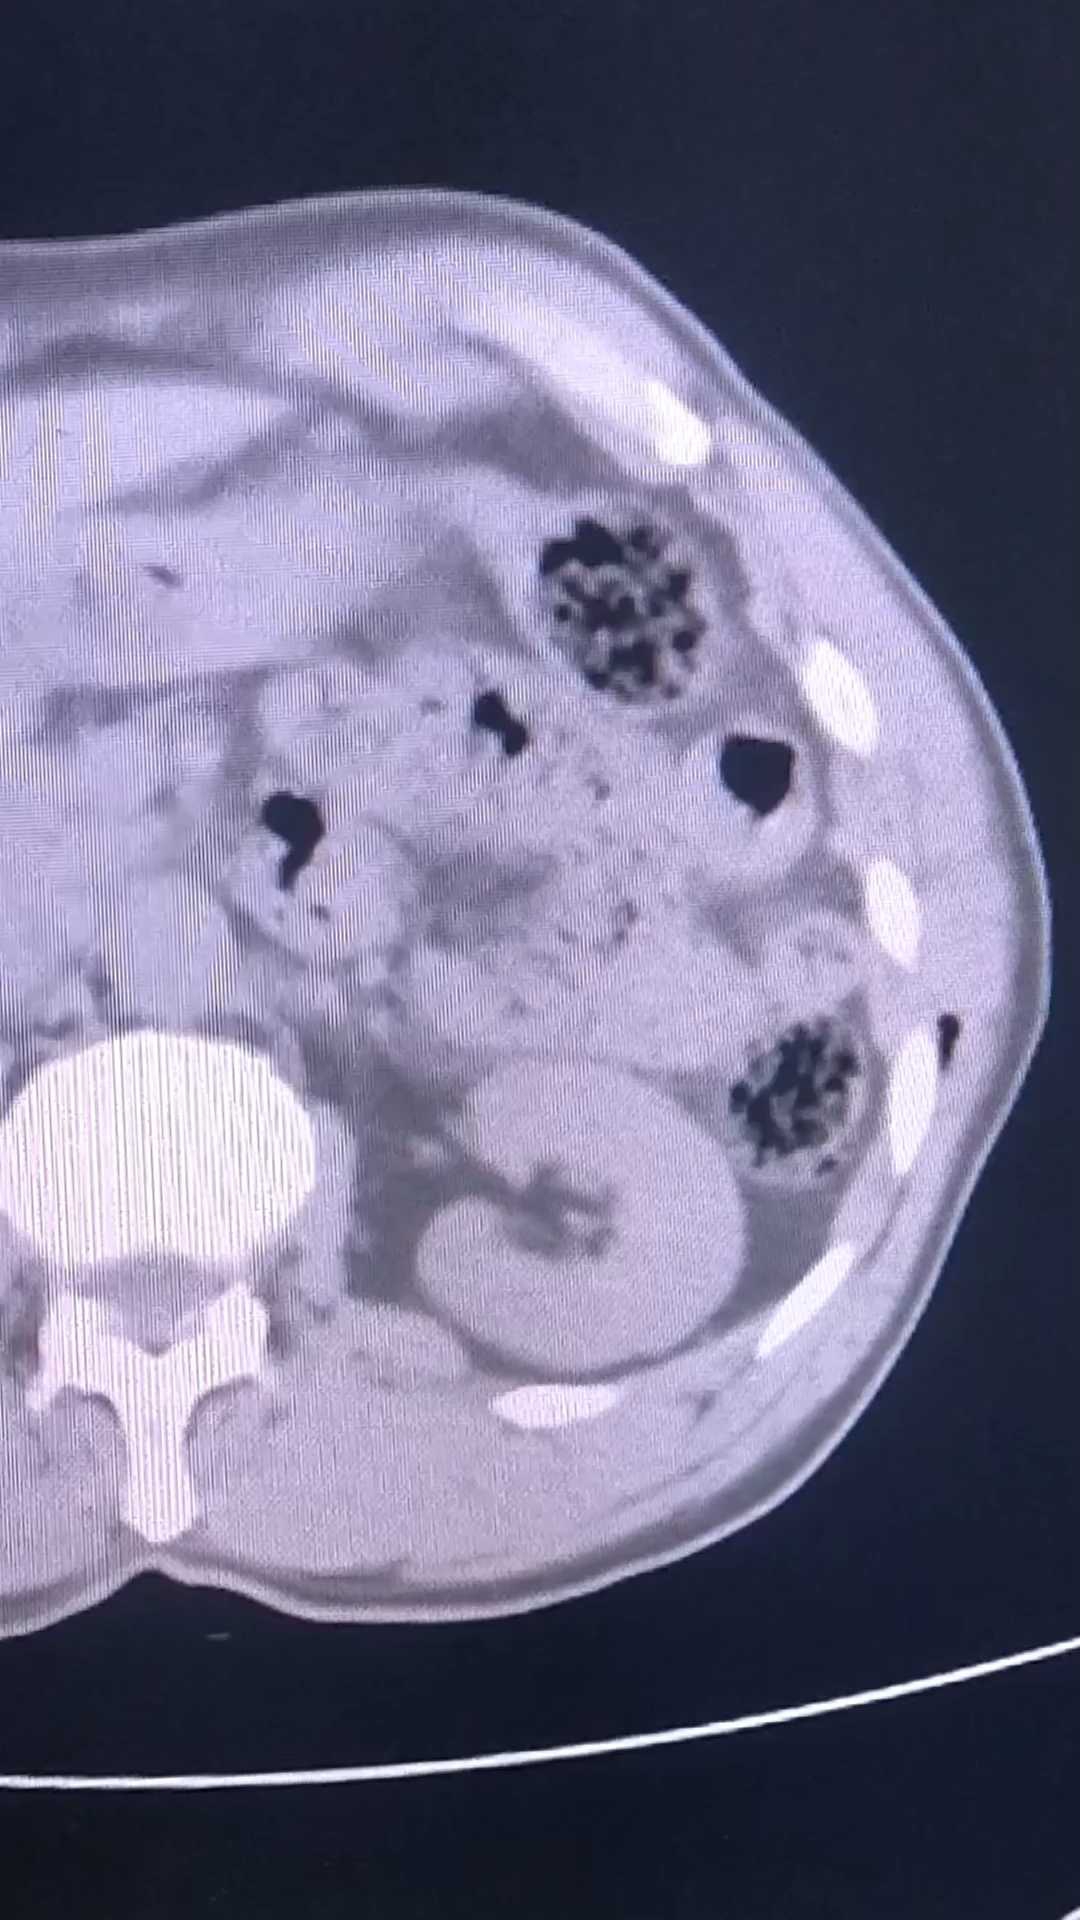

【治疗经过及结果】:急诊下完善腹部CT检查,未发现膈下游离气体,给予局麻下扩创探查,未探及腹膜损伤,随缝合治疗,术后3日常规复查,发现腹腔气体,无创面以外腹痛。